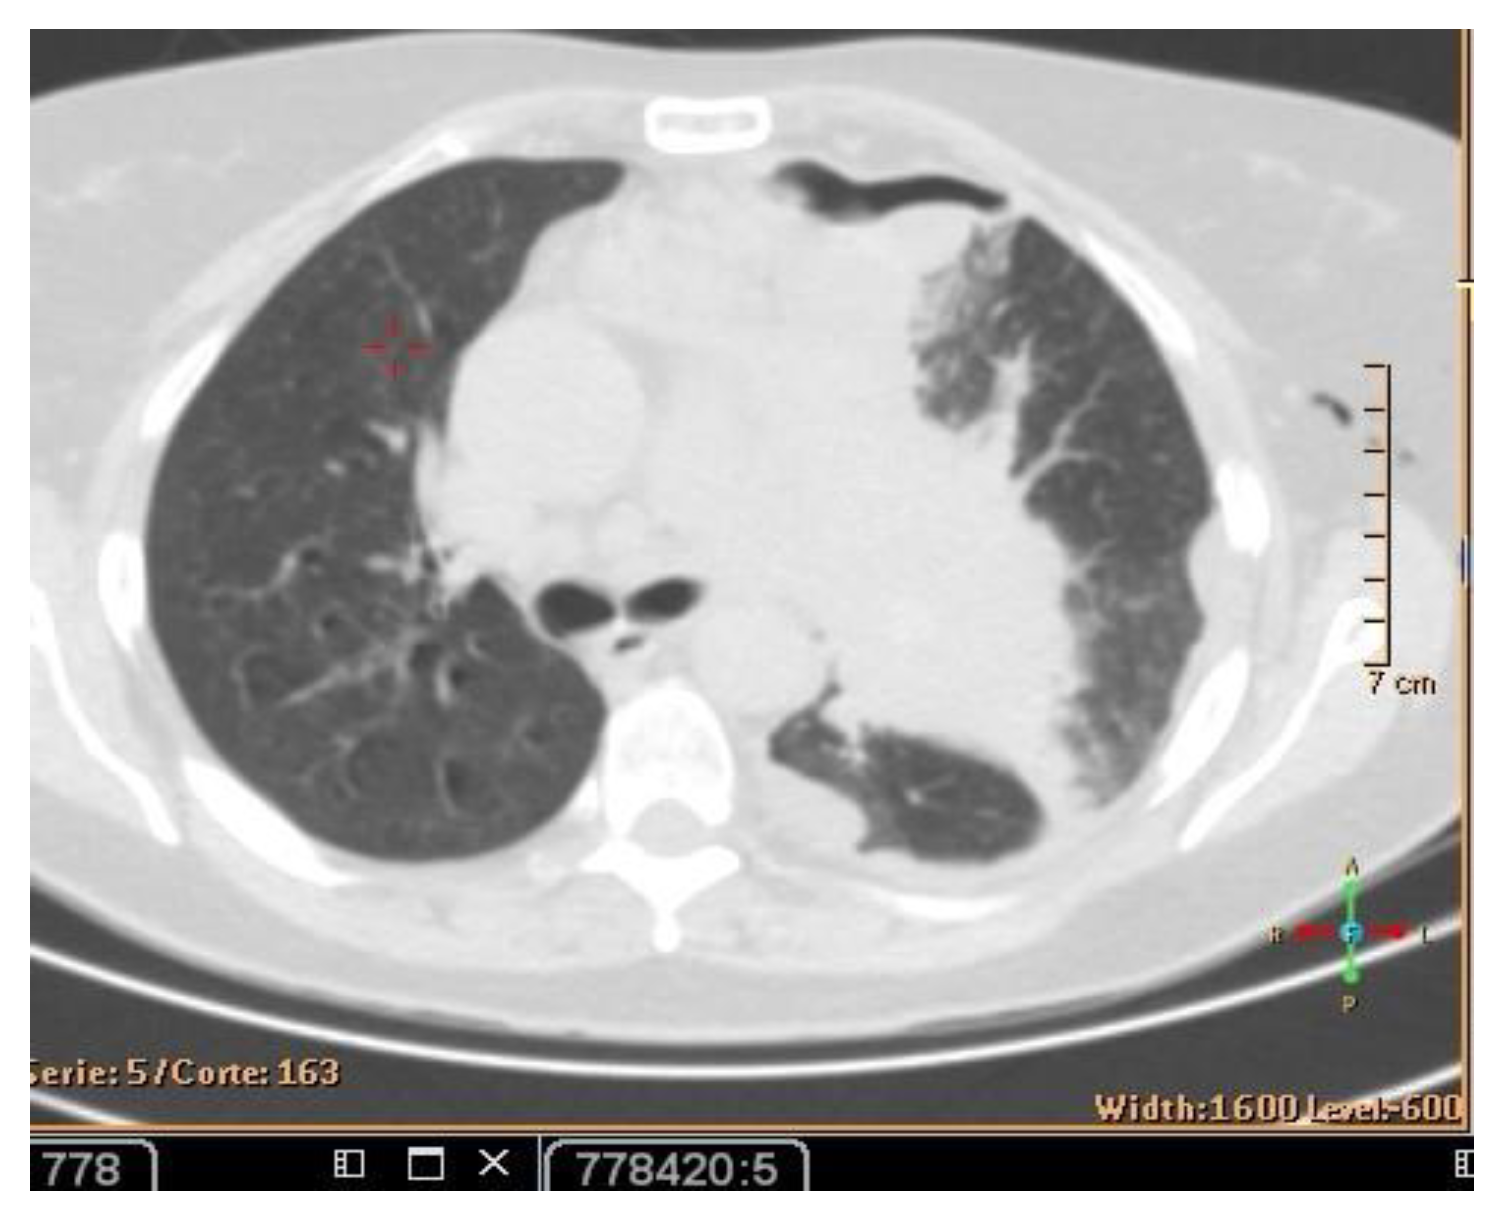

In July 2021, a 60-year-old patient came to our Cryosurgery unit, provided with a CT scan of the chest dated April 2021. The CT scan revealed the presence of a hyper-metabolic lesion with a size of 2.8 cm and involving the right upper/middle lobe related to the neoplastic process. The presence of hypermetabolic lytic bone lesions involving the right proximal femur T-10 and the left transverse process of T-9 was also confirmed, highlighting bone metastasis (Figure 4).

The process for patients with metastatic disease should include abdominal and pelvic CT scans. This is the reason why an abdominopelvic CT scan with contrast was performed in July 2021. There was no evidence of abdominopelvic metastases but always manifestations of diffusion of bone metastases. A specular nodule was noted in the right upper lobe with evidence of bilateral pulmonary nodules, and pleural and bone metastases. The pleural biopsy performed confirmed the presence of metastatic adenocarcinoma.

After three months of the cryoablation, specifically in November 2021, a control CT scan and Pet-CT was performed. An impressive reduction in the size of the tumor is noted (Figure 10).

Figure 10. PET-CT (left) and Ct scan(right) images after cryotherapy in the patient with lung cancer accompanied by bone metastases.